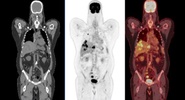

Быстро растущее использование препаратов — агонистов рецепторов GLP-1, применяемых при диабете и для снижения веса, может искажать результаты онкологических ПЭТ-КТ-исследований.Lenta.ru

Исследователи отметили повышенное накопление препарата в мышцах, сердце и бурой жировой ткани — эффект, который может быть ошибочно принят за опухоль или воспаление.Lenta.ru